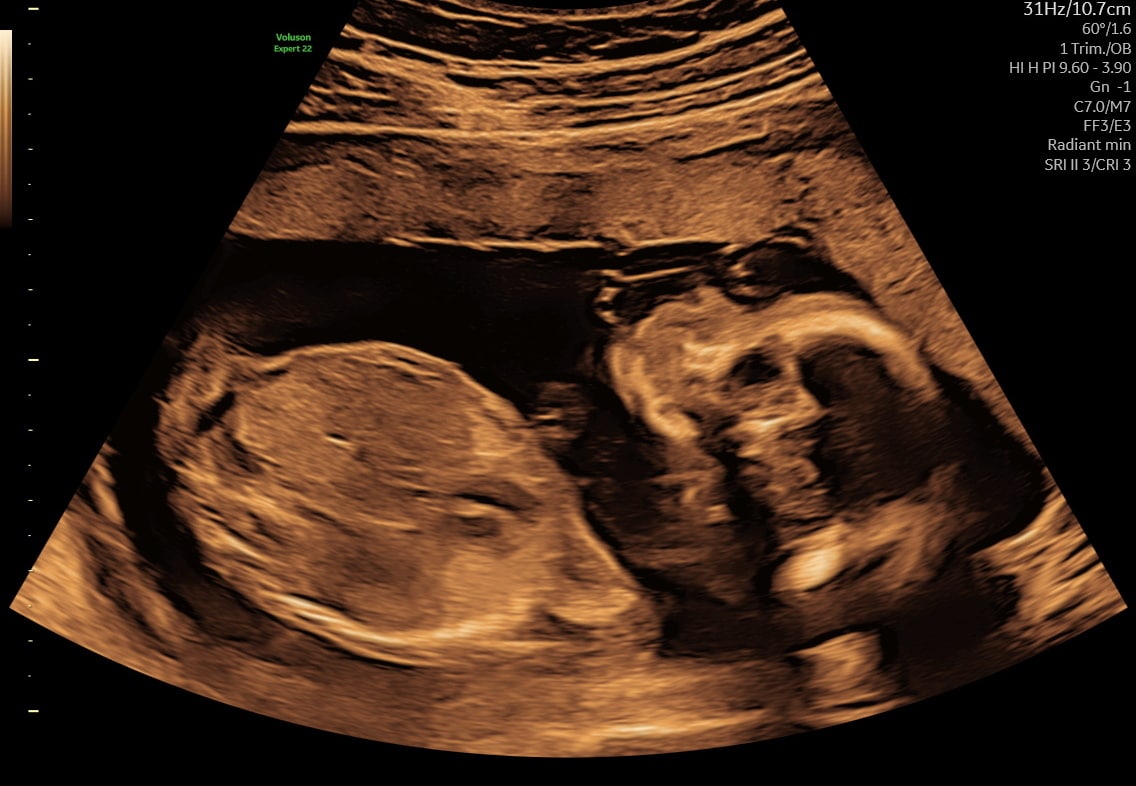

Første trimester (uge 5–13)

Bekræfter graviditetens placering, hjerteblink og antal fostre. Tidlig scanning fra uge 5+0.